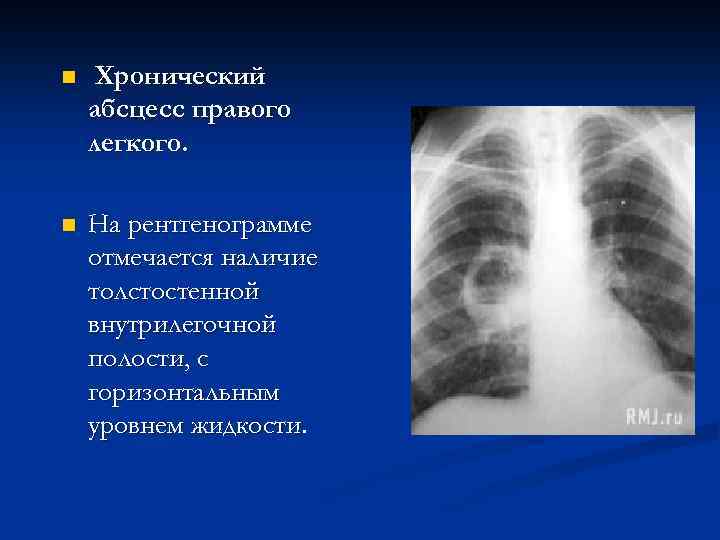

n Хронический абсцесс правого легкого. n На рентгенограмме отмечается наличие толстостенной внутрилегочной полости, с горизонтальным уровнем жидкости.